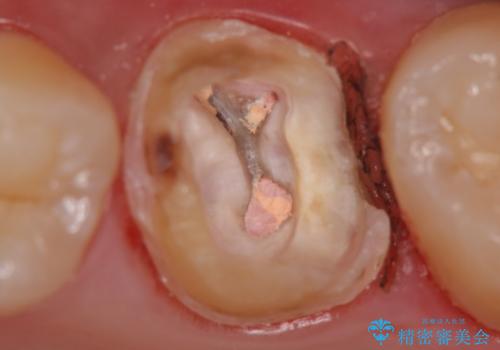

被せ物を除去し、根管治療を進めた後に新しい被せ物を装着していきます。

本来は歯茎をしっかりと下げる外科処置が適応となるケースでしたが、ご希望がなかったため最小限の侵襲に抑えて治療を行いました。

根の中を洗浄し、結果的に適合の良い被せ物をセットすることができました。